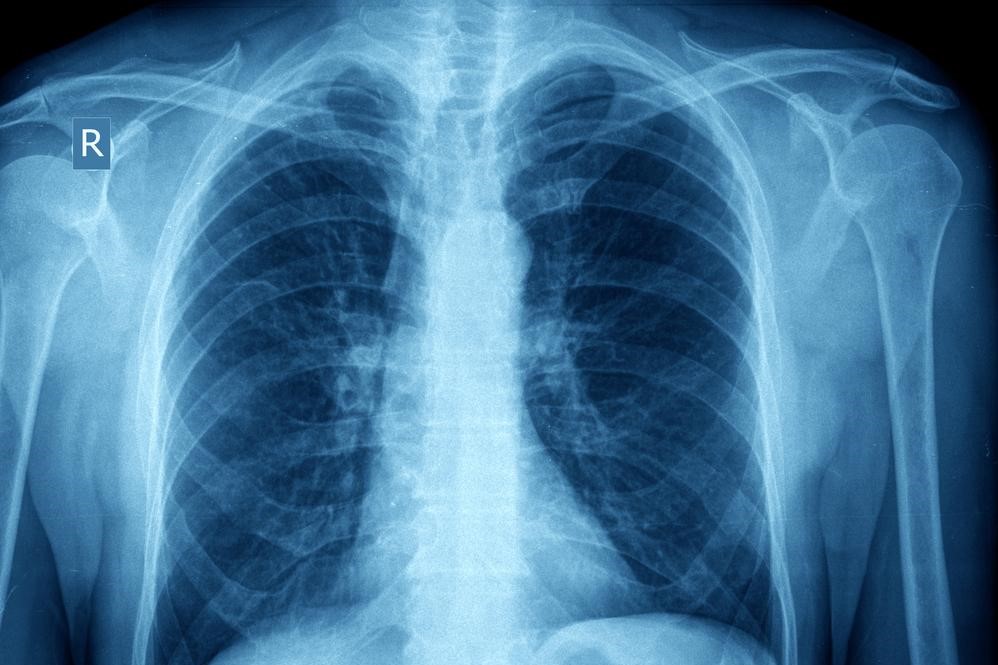

Pathology and Pathophysiology of Asthma

Asthma takes place in two forms; acute and chronic. Acute asthma, known as an asthma attack is an episodic event that occurs due to an asthma trigger. Chronic asthma develops due to the changes that occur from prolonged inflammation over time.

When a patient comes into contact with an asthma trigger, a chain reaction of events occur that leads to an asthma “attack.” The exposure to the trigger will cause the muscles that surround the airways to “clamp down” or contract, thus narrowing the spaces for air to travel through. In addition, the trachea and bronchial passageways will become inflamed with an increase in mucous production.

Patients will experience a rapid onset of symptoms such as shortness of breath, coughing, chest tightness, and wheezing.

It is believed that patients always have some degree of inflammation in the lungs that make them more sensitive triggers. Chronic inflammation over time can lead to changes in the structures of the lungs and increased mucous production. Proper control of asthma can limit these effects.